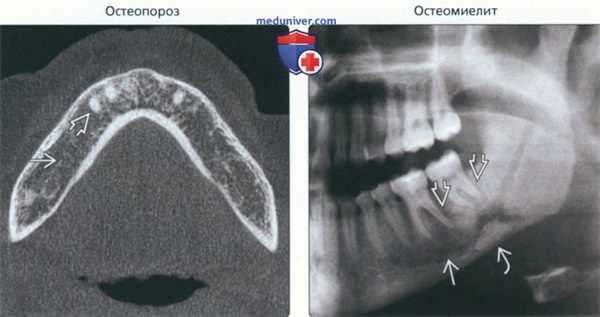

(Слева) На аксиальной КЛКТ у женщины 90 лет с остеопорозом определяются признаки остеопении нижней челюсти: разрежение трабекул, истончение или отсутствие твердой пластинки вокруг оставшихся зубов.

(Справа) На панорамной рентге нограмме определяются смешанные (литические и склеротические) изменения нижней челюсти слева. Обратите внимание на отсутствие твердой пластинки возле пораженных зубов и компактной кости вокруг нижнечелюстного канала. У нижнего края определяется секвестрация.